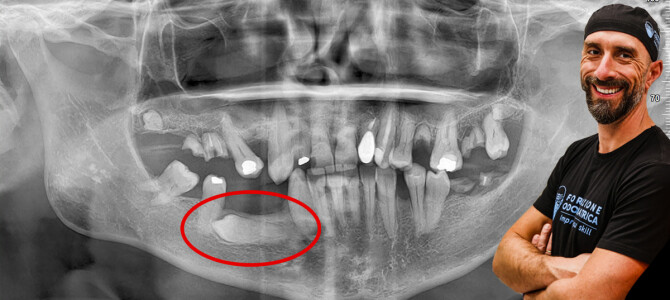

[VIDEO] Estrazione di un premolare distoverso incluso in mandibola

Non so come presentare questo caso, se come semplice o difficile. Con tutta la modestia del mondo a me sembra un'estrazione assolutamente banale ma il fatto che sia finita sulla mia agenda e non sia stata fatta dai collaboratori che si occupano di estrazioni di…